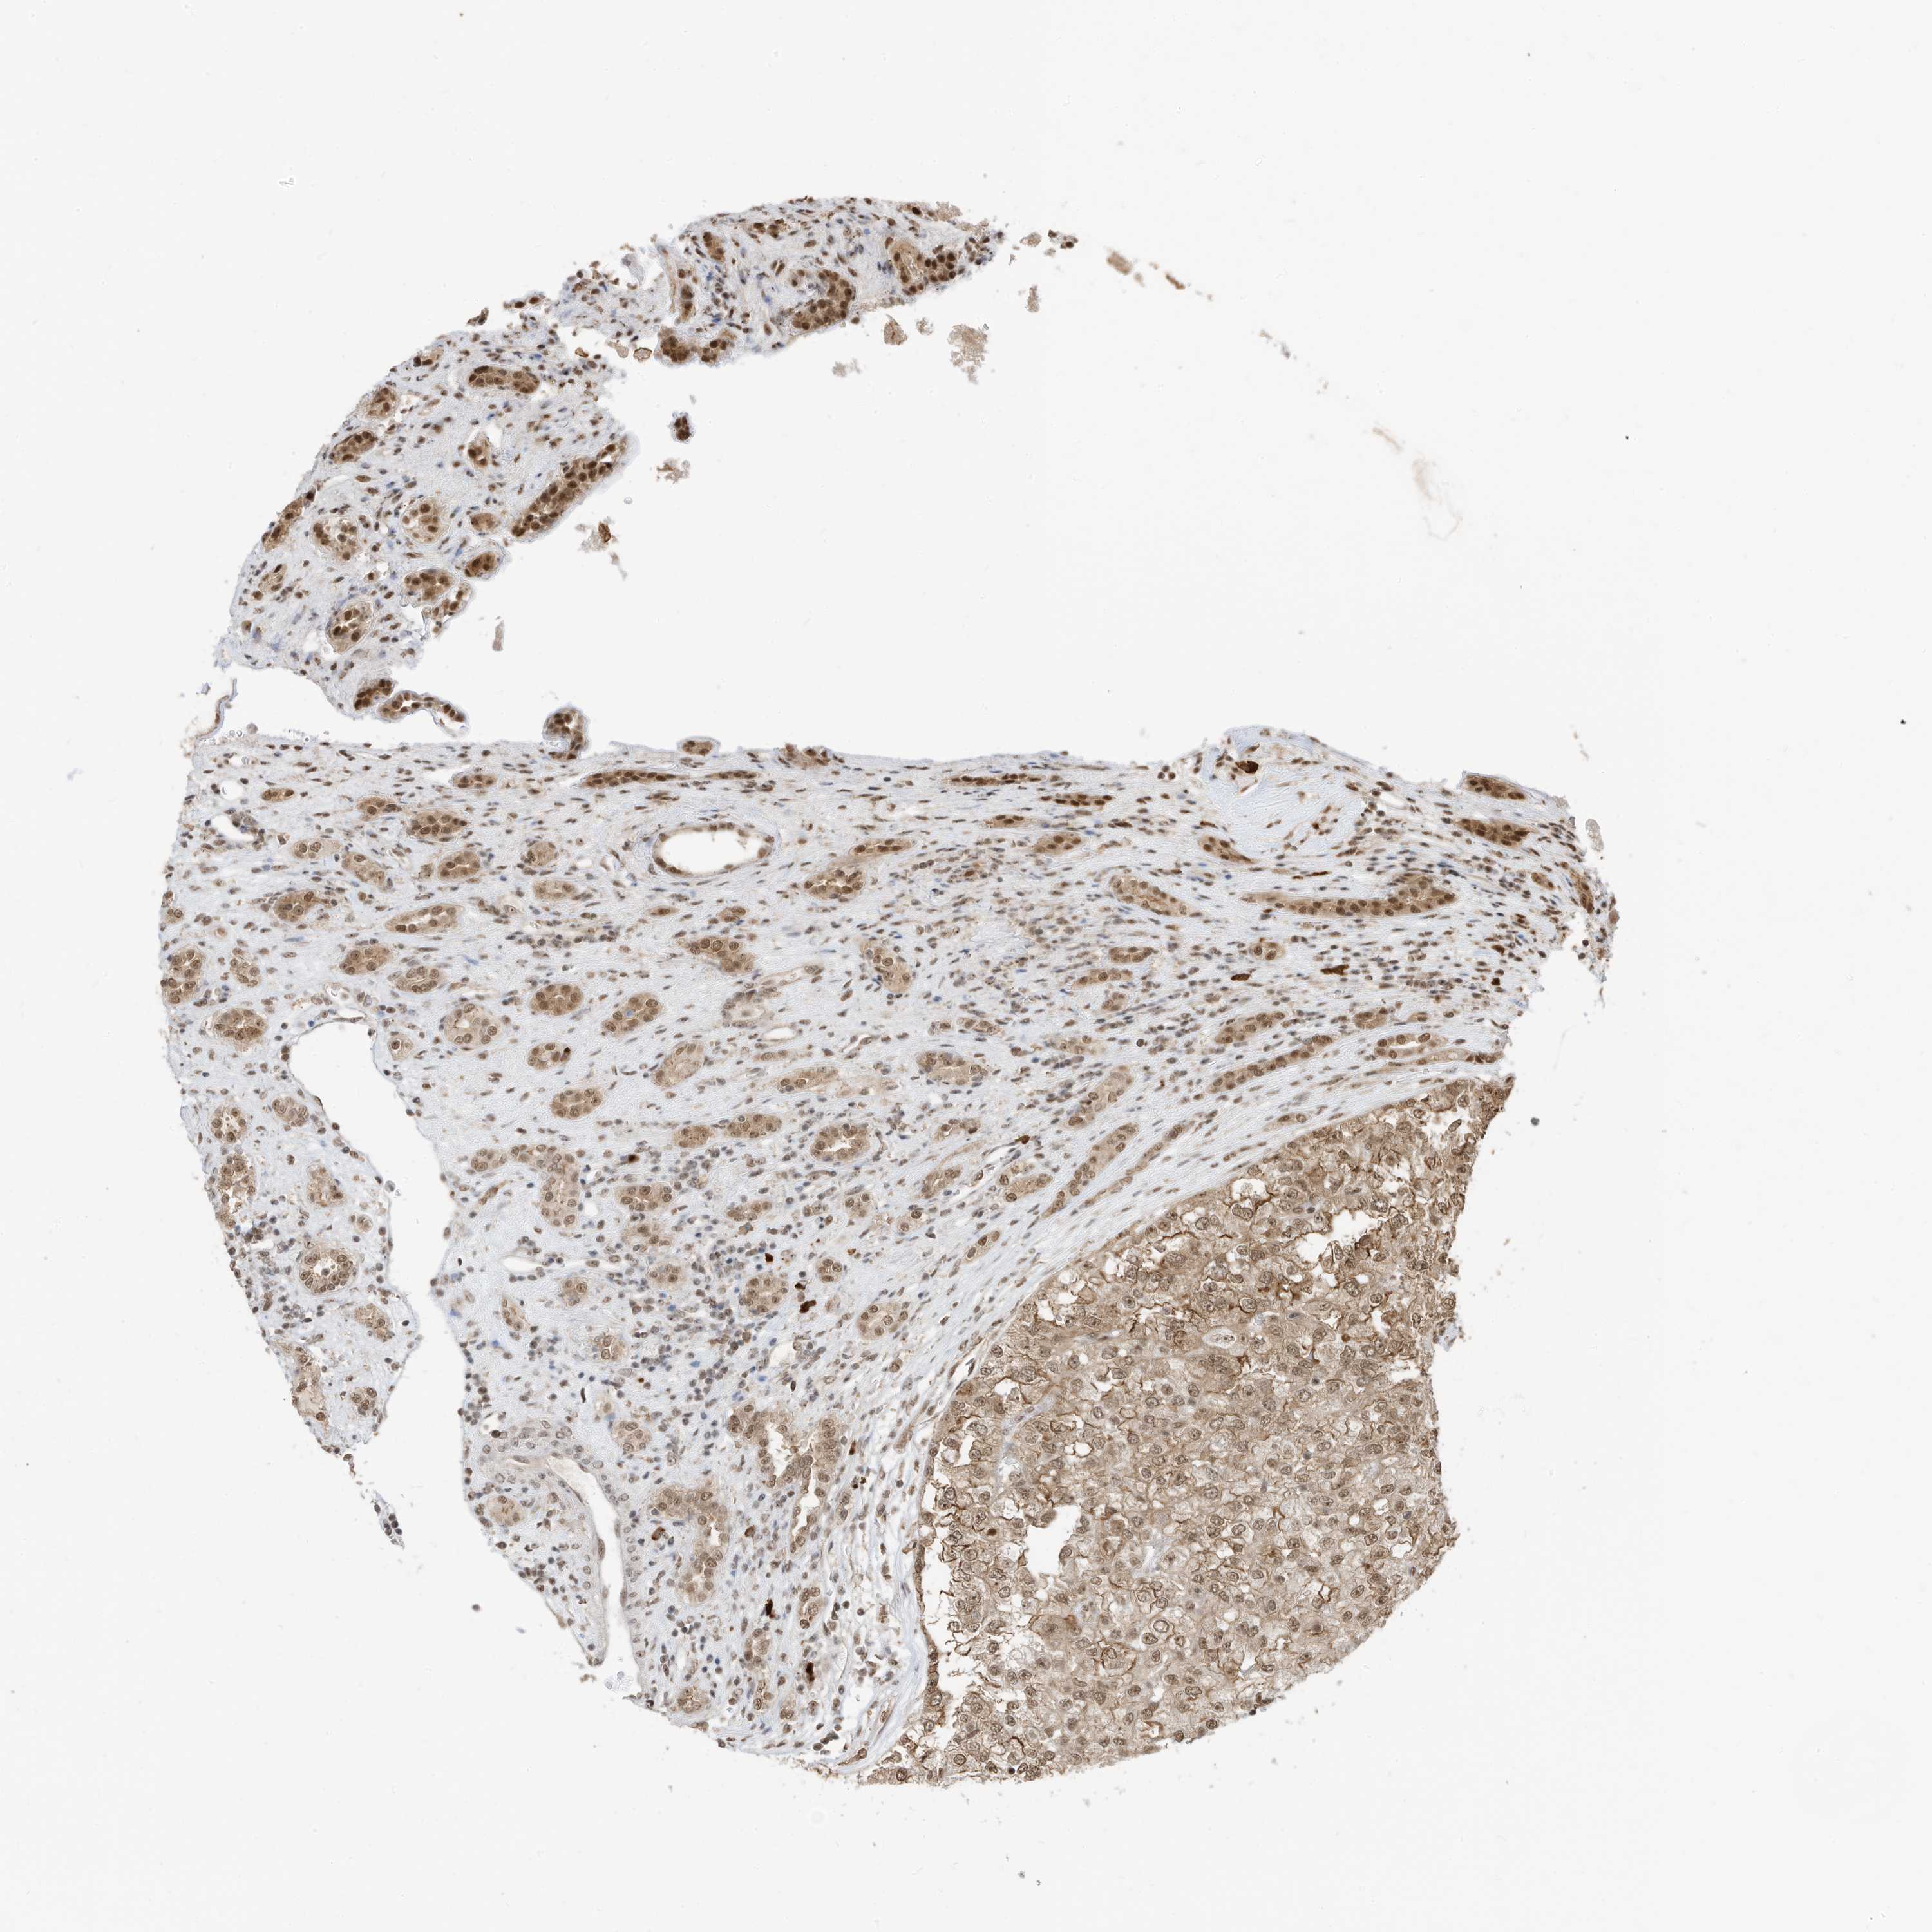

KIDNEY RENAL CLEAR CELL CARCINOMA (VALIDATION) - Interactive survival scatter ploti

The Survival Scatter plot shows the clinical status (i.e. dead or alive) for all individuals in the patient cohort, based on the same data that underlies the corresponding Kaplan-Meier plots. Patients that are alive at last time for follow-up are shown in blue and patients who have died during the study are shown in red.

The x-axis shows the expression levels (FPKM) of the investigated gene in the tumor tissue at the time of diagnosis. The y-axis shows the follow-up time after diagnosis (years). Both axes are complimented with kernel density curves demonstrating the data density over the axes. The top density plot shows the expression levels (FPKM) distribution among dead (red) and alive patients (blue). The right density plot shows the data density of the survived years of dead patients with high and low expression levels respectively, stratified using the cutoff indicated by the vertical dashed line through the Survival Scatter plot. This cutoff is automatically defined based on the FPKM cutoff that minimizes the p-score. The cutoff can be changed by dragging the vertical line or by entering a cutoff value in the square labeled "Current cut-off".

Under the Survival Scatter plot the p-score landscape (black curve; left axis) is shown together with dead median separation (red curve; right axis). Dead median separation is the difference in median mRNA expression between patients who have died with high and low expression, respectively. It is calculated as follows: median FPKM expression of dead patients with high expression - median FPKM expression of dead patients with low expression. This is intended to aid the user in visually exploring custom cutoffs and the associated p-scores and dead median separation.

Individual patient data is displayed and can be filtered by clicking on one or more of the category buttons on the top of the page. Categories describing expression level and patient information include: high, low, alive, dead, female, male and tumor stages. The scale of the x-axis can be toggled between linear and log-scale by clicking on the "x log" button. Mouse-over function shows TCGA ID, patient information and mRNA expression (FPKM) for each patient.

& Survival analysisi

Kaplan-Meier plots summarize results from analysis of correlation between mRNA expression level and patient survival. Patients were divided based on level of expression into one of the two groups "low" (under cut off) or "high" (over cut off). X-axis shows time for survival (years) and y-axis shows the probability of survival, where 1.0 corresponds to 100 percent.

ZNF195 is not prognostic in Kidney Renal Clear Cell Carcinoma (validation)

Best expression cut offi

Based on the FPKM value of each gene, patients were classified into two groups and association between prognosis (survival) and gene expression (FPKM) was examined. The best expression cut-off refers the FPKM value that yields maximal difference with regard to survival between the two groups at the lowest log-rank P-value. Best expression cut-off was selected based on survival analysis .

When clicking on this number, the vertical dashed line indicating cut-off, the interactive survival plot, and the Kaplan-Meier curve will be adjusted to show results based on the best expression cut-off.

: 12.21

Median expressioni

Median expression refers to the median FPKM value calculated based on the gene expression (FPKM) data from all patients in this dataset. When clicking on this number, the vertical dashed line indicating cut-off, the interactive survival plot, and the Kaplan-Meier curve will be adjusted to show results based on the median expression.

: N/A

Median follow up timei

Median follow up time refers to the median time (years) after diagnosis with this type of cancer, based on clinical data from all patients in this dataset.

P scorei

Log-rank P value for Kaplan-Meier plot showing results from analysis of correlation between mRNA expression level and patient survival.

N/A

5-year survival highi

5-year survival for patients with higher expression than the expression cutoff.

For melanoma and glioma, 3-year survival is shown.

5-year survival lowi

5-year survival for patients with lower expression than the expression cutoff.

TCGA RNA samplesi

RNA-seq data is reported as average FPKM (number Fragments Per Kilobase of exon per Million reads), generated by the The Cancer Genome Atlas (TCGA) .

Normal distribution across the dataset is visualized with box plots, shown as median and 25th and 75th percentiles. Points are displayed as outliers if they are above or below 1.5 times the interquartile range. FPKM values of the individual samples are presented next to the box plot.

Average pTPM 15.0

Number of samples 100